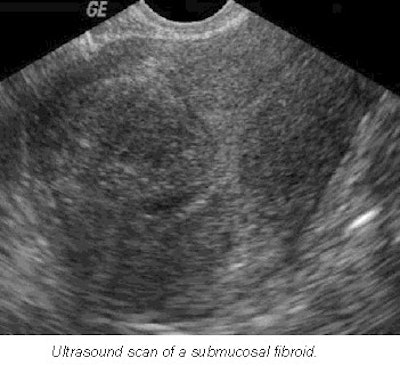

Making an accurate diagnosis of fibroids is extremely important because there are many ways of treating them. Thirty percent of women with fibroids have bleeding, particularly when the fibroids are submucosal in location.

- Women with menorrhagia, increased volume or duration of bleeding, are far more likely to have adenomyosis than fibroids. Ultrasound features for fibroids include one or more discrete masses with a hypoechoic halo (compressed myometrium), diffuse posterior shadowing, and calcification in late stages or after pregnancy. However, cysts are uncommon.

- Fibroids can be hypoechoic, isoechoic (same echogenicity as myometrium), or hyperechoic. In comparison, the characteristics of adenomyosis include ill-defined regions of mixed textural changes, asymmetric myometrial thickening, streaky shadowing posteriorly, and no calcifications.